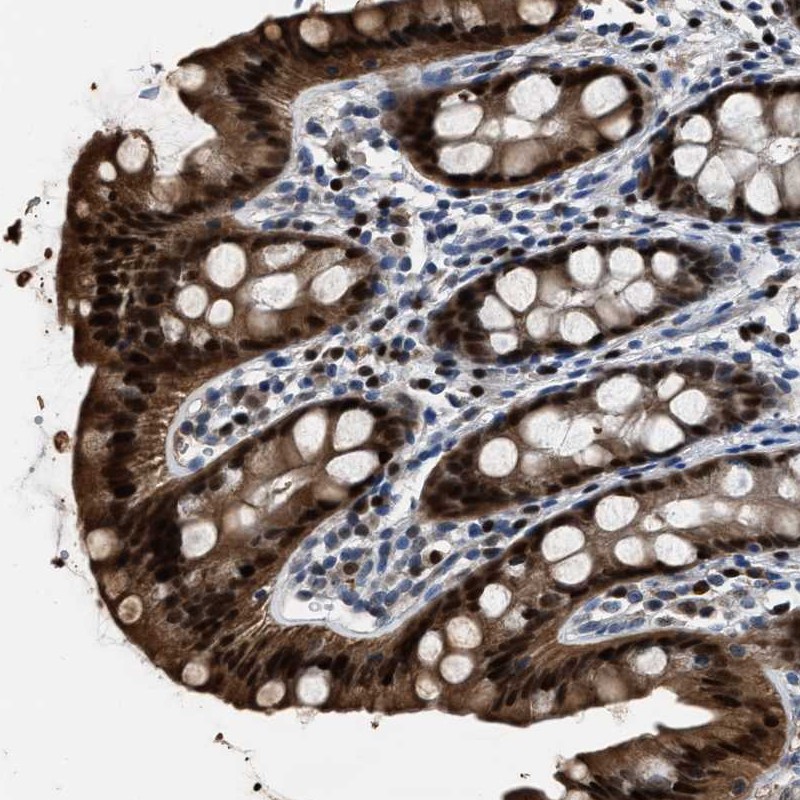

Immunohistochemical staining of human rectum shows strong nuclear and cytoplasmic positivity in glandular cells.